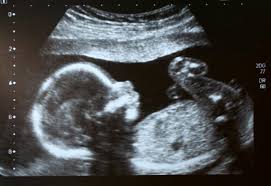

His now ex-girlfriend had an abortion on his baby against his wishes at the clinic in February 2017 when she was six weeks pregnant, according to legal papers filed in the case. The case, involving a girl who reports say was 16 when she became pregnant to Magers, then aged 19, has alarmed abortion advocates.

Fox reported that Magers was able to file the lawsuit because voters in Alabama recently passed an amendment to its constitution to recognise the personhood of an unborn baby months earlier.